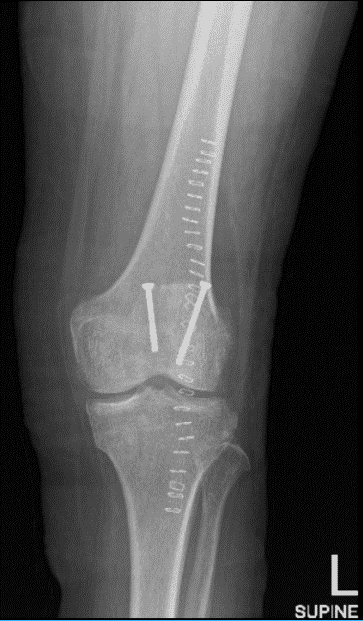

Un paciente de 68 años estaba en nuestra consulta con quejas, las radiografías postoperatorias en la revisión mostraron cortes en los tornillos y fallo en la fijación con desplazamiento de la fractura. El Dr. Karkare habló sobre las opciones de tratamiento y el paciente optó por el manejo quirúrgico en forma de revisión.

El paciente fue atendido para una visita de seguimiento y presentó resultados de radiografía que mostraron cambios postquirúrgicos sobre la rótula con una posición satisfactoria del hardware. Por lo demás, un examen poco destacable.

Radiografía de rodilla izquierda AP y lateral